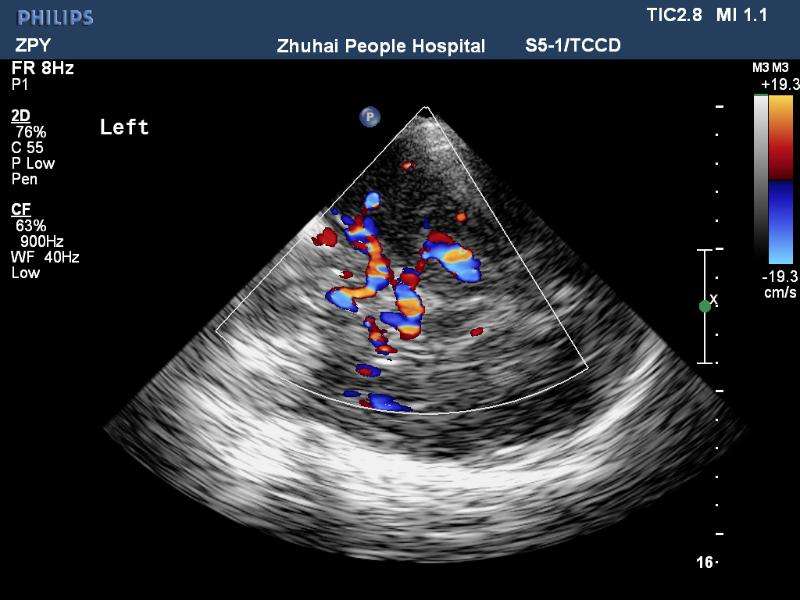

經(jīng)顱彩色編碼雙功能超聲(transcranial color-coded duplex sonography

TCCD)是一種非侵入性發(fā)現(xiàn)顱內(nèi)動(dòng)脈異常血流動(dòng)力學(xué)狀態(tài)的可靠方式。TCCD成像原理是在TCD基礎(chǔ)上增加了二維灰階實(shí)時(shí)顯像以及彩色編碼雙功能超聲成像,在二維顯示顱內(nèi)解剖結(jié)構(gòu)的同時(shí),同時(shí)對(duì)運(yùn)動(dòng)紅細(xì)胞產(chǎn)生的多普勒頻移進(jìn)行彩色編碼。應(yīng)用TCCD檢測(cè)時(shí)可以通過在感興趣區(qū)內(nèi)多點(diǎn)取樣,得出取樣容積內(nèi)多普勒頻移曲線,通過雙側(cè)對(duì)比、左右對(duì)比以及前后對(duì)比,綜合評(píng)價(jià)缺血性腦血管病受檢者Willis環(huán)的血流動(dòng)力學(xué)變化。